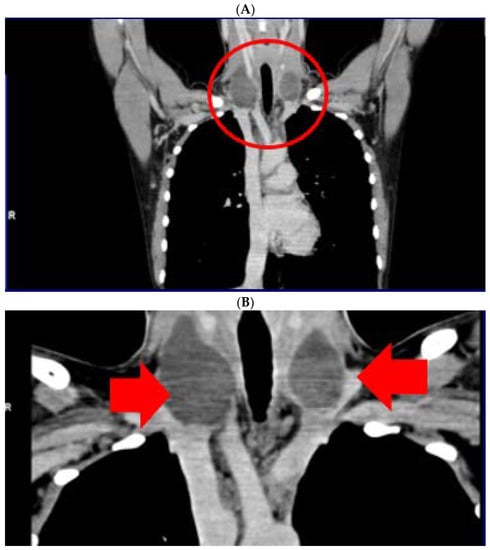

Neck computed tomography confirmed bilateral, lateral cervical, well-shaped masses with cystic appearance, of oval form (of 40/25/57.4 mm on the right, respective of 1.6/27/40 mm on the left). (Figure 3).

Figure 3.

Computer tomography of neck area showing bilateral lateral cervical well-shaped masses with cystic features of 4 by 2.5 by 5.74 cm on the right, respective of 1.6/2.7/4 cm on the left (5 weeks since surgery, before any local intervention). (A). Frontal plane—first section; (B). Frontal plane—second section; (C). Transverse plane; (D). Sagittal plane.